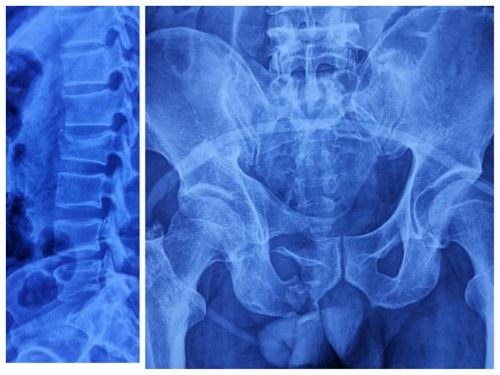

术前x线显示:骨盆、耻骨上下支、骶骨、腰2椎体骨折。

术前ct显示:骶骨骨折累及骶髂关节面。